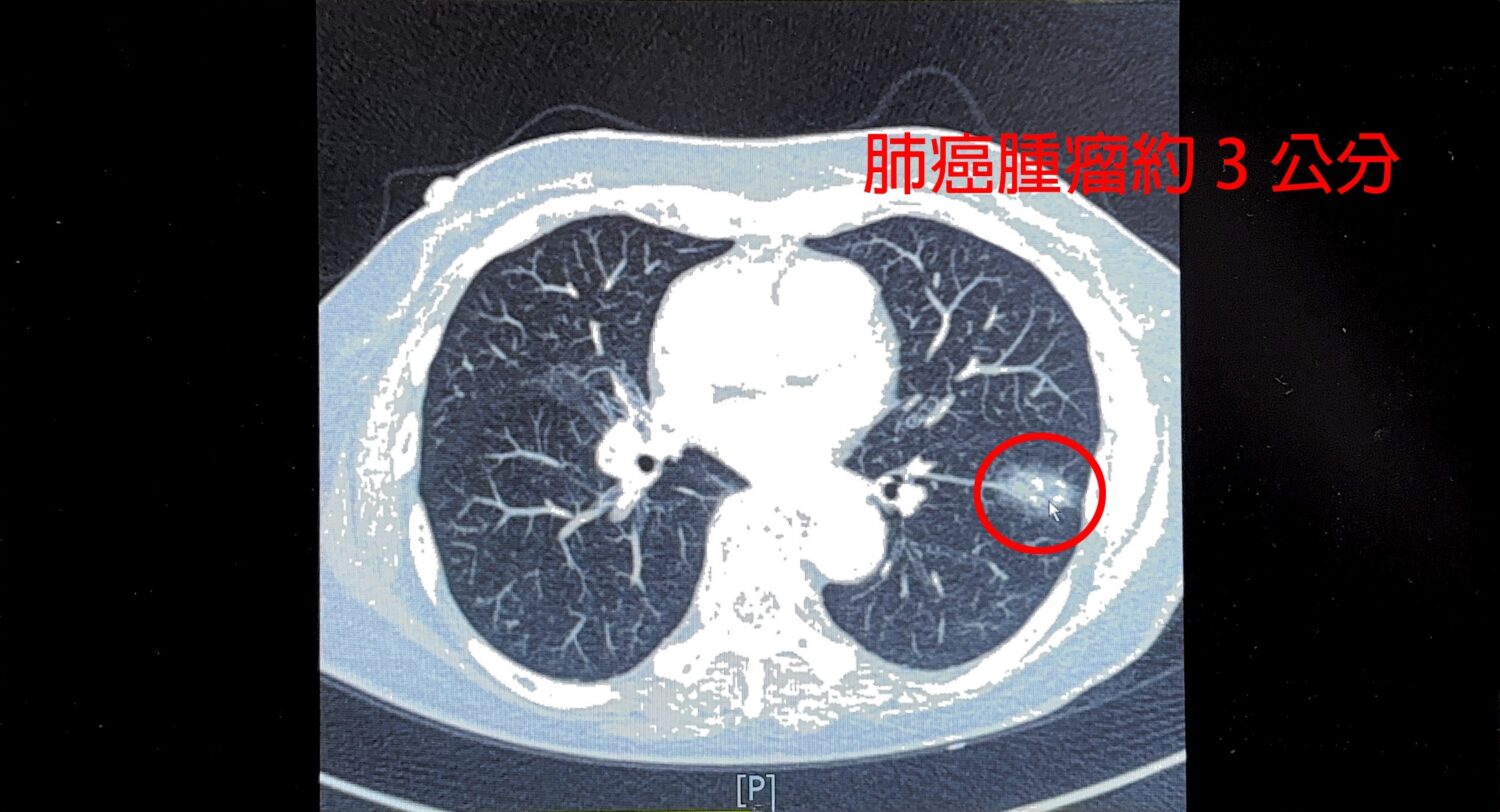

【警政時報 張家燁/新竹報導】一位75歲女性平時不菸不酒,今年於健康檢查安排LDCT肺癌篩檢,意外發現左下肺葉近3公分惡性腫瘤,求診中國醫藥大學新竹附設醫院胸腔外科謝義山醫師,經醫病溝通後,執行達文西微創手術,歷經4小時完成切除,病患術後三天順利出院,恢復情況良好。

謝義山醫師指出,患者十多年前曾罹患肺結核,導致肺部縱膈淋巴結硬化並與血管沾黏,手術中稍有不慎恐大出血,透過達文西機械手臂輔助,順利完成血管分離結紮,最終僅200cc出血,展現精準醫療優勢,術後建議病患逐步恢復日常,兩週可輕便活動,2至3個月後再進行重度運動。

謝醫師提醒,曾感染肺結核患者因肺部殘留病灶,罹患肺癌風險較一般人高出40至200倍,台灣女性肺癌患者中,80%至90%為不菸不酒族群,顯示基因遺傳及肺部結節也是重要風險因子,而有結核病史或家族史的女性,務必每年接受低劑量胸部電腦斷層篩檢,早期發現才能提高治癒率,肺癌初期常無明顯症狀,但若出現慢性咳嗽、咳血、胸痛、聲音沙啞、不明體重下降或反覆肺炎,應及早就醫。